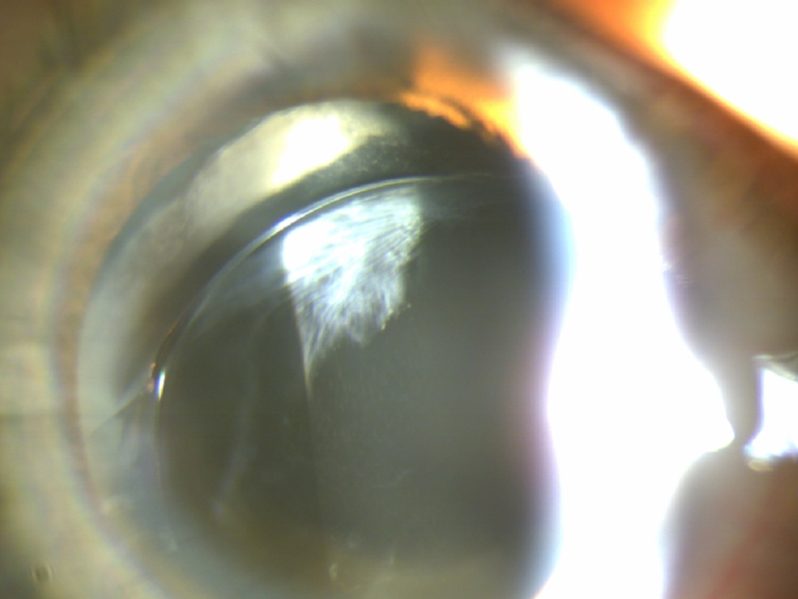

피질백내장 수술

77세 여성 환자 사례

수술 1개월 후 나안시력 0.8

수술 전

수술 후

※ 해당 이미지는 본원에서 직접 촬영한 사진입니다.